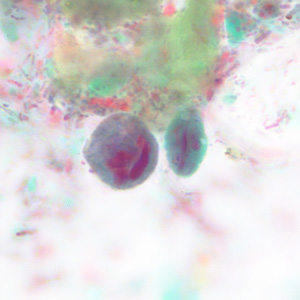

Within a week of returning from a conference in Mexico, a 28-year-old woman presented to her primary care physician with cramps, abdominal pain, gas and diarrhea. A routine Ova and Parasite (O&P) examination was performed on stool specimens. Figures A–F show objects observed on a trichrome-stained slide prepared from the stool. All images were taken at 1000x oil magnification. The objects in Figures A–C measured 12 micrometers. The objects in Figures D and E averaged 10 micrometers. The object in Figure F measured 12 micrometers in diameter. What is your diagnosis? Based on what criteria?

Figure D

Figure E